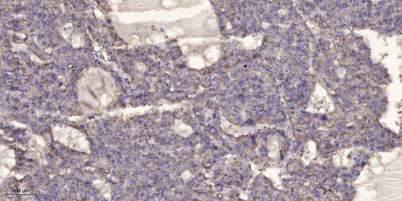

Applications’╝ÜWB;ELISA;IHC

Õģ│µ│©ÕŠ«õ┐ĪÕģ¼õ╝ŚÕÅĘ

ÕŠ«õ┐Īµē½õĖƵē½Ķ┐×Õ┐ÖÕÆ©Ķ»ó

ÕŠ«õ┐Īµē½õĖƵē½Ķ┐×Õ┐ÖÕÆ©Ķ»ó